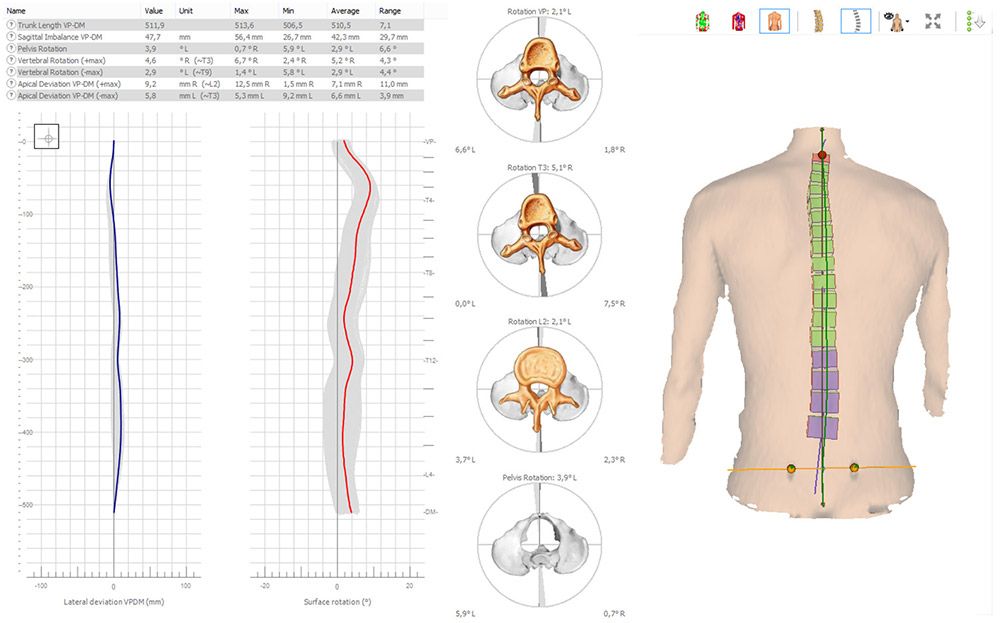

Оптическая диагностика позвоночника Diers: изображения и технологии